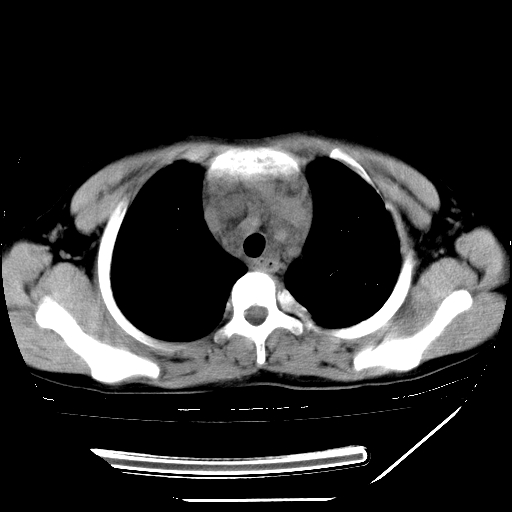

男,13岁,咳嗽、咳痰伴发热一周。

上纵隔课件多枚淋巴结,部分相互融合,左侧支气管壁增厚,肺纹理较右侧增粗,患者,男,13岁,

中上纵隔见多枚淋巴结肿大,部分相互融合成团片,左肺门增大,上叶支气管变窄,肺内多处斑片状 索条状及棉絮状致密影。临床“男,13岁,咳嗽、咳痰伴发热一周。”首先考虑:原发综合征!不除外淋巴瘤可能!